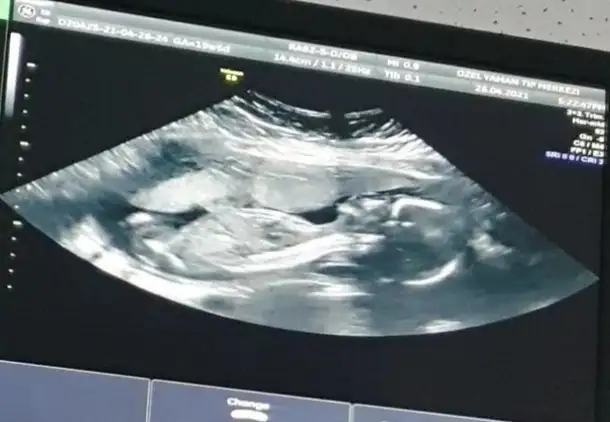

Emin olmadım sanki erkek gibi başka USG varsa paylaşınMerhaba, bizim icin de bir tahmininiz olur mu acaba? Normalde 12+4 ama ultrasonda 13+3 cikiyor. Allah nasip ederse gelecek ayin 20sinde kesin ogrenecegiz cinsiyeti. Yarin Nifty testi icin kan verecegim

Net değil USG başka varsa paylasinDr emin olamadan bir tahmin yaptı ama buraya da atayım dedim11+6 dedi

11+4 ŞuanŞimdilik erkek yönünde ama en iyi 11 12 13 haftalar olmalı